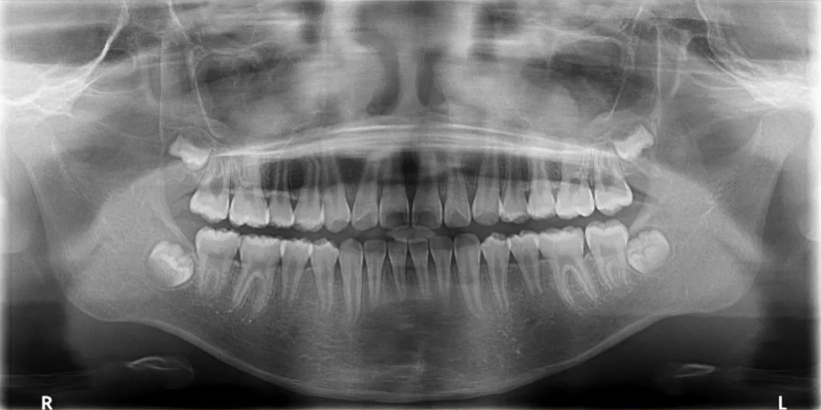

32岁,男性,因咬物不适来院就诊。

查:14残根,牙龈红肿;35叩诊(+),45叩诊(+),牙颌面见畸形中央尖。

曲面断层片怎么看口腔精读 | 一次性教你看懂曲面断层片!_https://www.jmylbn.com_新闻资讯_第20张

35叩诊(+)

二次拍根尖片确认可看到根尖低密度炎症,临床检查与影像学检查相符,是根尖周炎。

曲面断层片怎么看口腔精读 | 一次性教你看懂曲面断层片!_https://www.jmylbn.com_新闻资讯_第21张

临床检查时发现14残根,牙龈红肿。曲面断层片上由于前磨牙转角问题,看不到残根,无法明确到底有没有残根,无法通过曲面断层片进行确诊或评估。

曲面断层片怎么看口腔精读 | 一次性教你看懂曲面断层片!_https://www.jmylbn.com_新闻资讯_第22张

这时需要加拍根尖片,很明显能看到残根。这就说明,有曲面断层片也不能排除情况。

临床检查45叩诊(+),牙颌面见畸形中央尖。加拍根尖片可看到,右下5根方有低密度影,并且右下5的牙根较短小,和曲面断层片上显示的大小不同,所以右下5是舌向倾斜的牙齿。